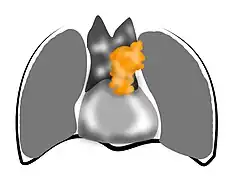

Le thymus est un organe intrathoracique, situé dans la loge thymique, dans le médiastin antérieur[3]. Cette zone est située entre les poumons, et à l'avant du cœur et des gros vaisseaux tels que l'aorte et ses branches[4]. Le thymus est constitué de deux lobes unis par le milieu, sauf à leurs extrémités supérieure et inférieure, appelées les cornes thymiques[5]. Le thymus comprend une région superficielle, appelée « cortex », et une région profonde, appelée « médulla ». Il grandit de la naissance jusqu’à la puberté, puis régresse progressivement[6].

Les thymomes sont rares, avec une fréquence de 0,15 cas pour 100 000 habitants et par an dans le monde[14],[15]. On recense environ 250 nouveaux cas par an en France[16],[17]. Il s'agit toutefois des tumeurs du médiastin antérieur les plus fréquentes (50 % des cas sont des thymomes). Plus de 90 % des tumeurs thymiques sont situées dans le médiastin antérieur (la région située entre les poumons et à l'avant du cœur et des gros vaisseaux), les autres étant dans la région cervicale ou les autres régions du médiastin[14].

Les examens d'imagerie réalisés comprennent en général en premier lieu une radiographie thoracique, puis un scanner thoracique[28]. L’envahissement des ganglions et les métastases doivent être recherchés au cours du bilan[14].

La radiographie thoracique permet de visualiser entre 45 % et 80 % des tumeurs thymiques[29]. De face, elles présentent un aspect bien délimité, parfois lobulé, débordant d'un côté du médiastin. Le profil permet d'affirmer le caractère rétrosternal de la tumeur, et donc sa localisation dans le médiastin antérieur. Les signes d'envahissement sont rares et peu visibles, et comprennent principalement l'ascension d'une coupole diaphragmatique, faisant suspecter un envahissement du nerf phrénique[28].